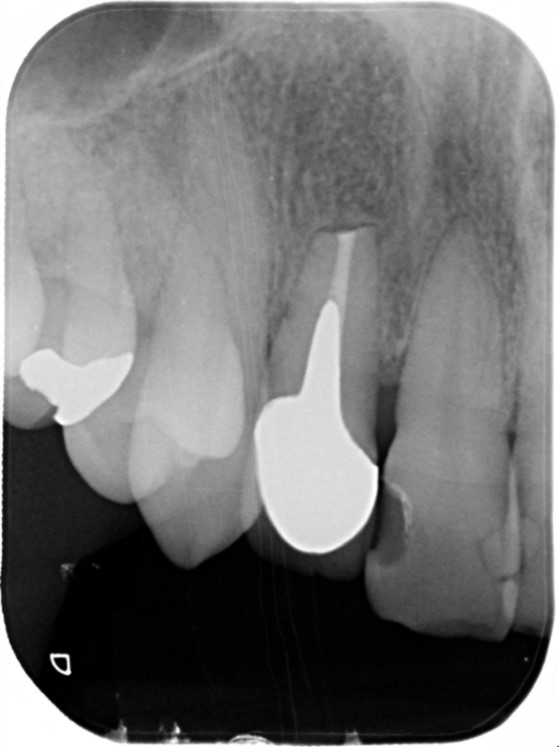

2023/1 根に穴が開いていました。

2023/8 根っこの治療が終わり、しっかり土台ができました。

治療部位 | 右上5番 |

費用 | 約93000円 |

治療期間 | 7ヶ月 |

注意事項(リスク・副作用など) | 根管治療を行うためには通常の虫歯治療と違い、歯を大きく削る必要性が出ます。これにより薄くなった歯は脆くなってしまいます。 |

カテゴリ | 歯内療法 |

マイクロスコープ、ラバーダムを使用して根管治療を行いました。